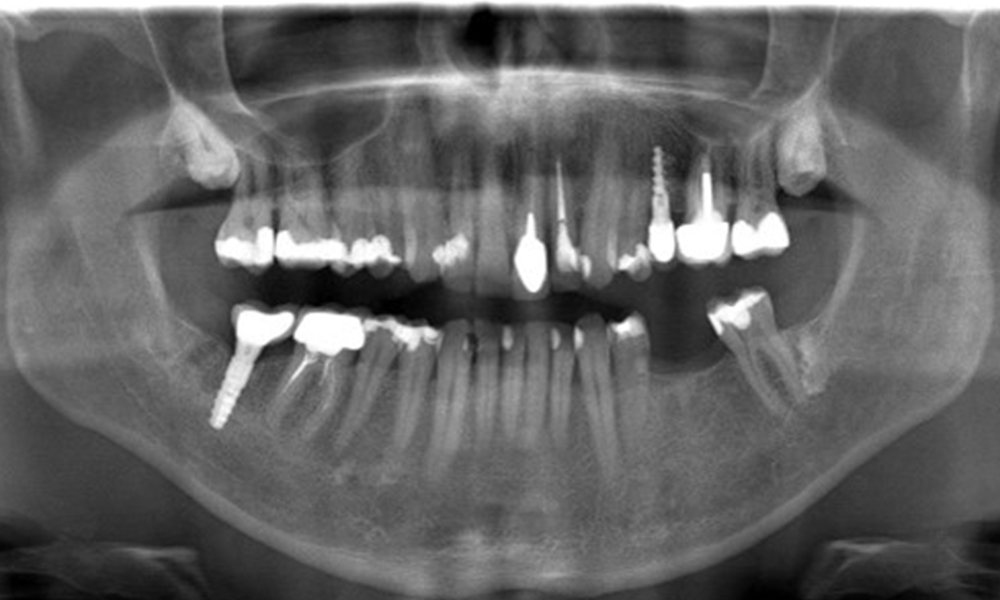

In the medical history, the 55-year-old patient states that he has no systemic disease and is not taking any medication. The patient’s lifestyle is similarly unremarkable. The patient has a few tooth restorations and two implants (2nd and 4th quadrants). On the basis of current findings, gingivitis is identified in an otherwise stable periodontal condition on the reduced periodontium (stage III, grade A).

The X-ray images show the bone loss.

OPG: 29/02/2024